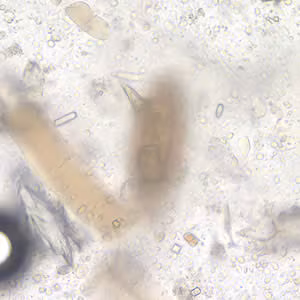

A missionary traveled to various countries in sub-Saharan Africa for one year. He went to his physician complaining of abdominal pain and occasional diarrhea which he experienced since his return to the U.S. He reported he swam in various lakes while he was abroad. An ova and parasite (O & P) stool examination revealed objects, measuring 135 µm, like the one shown in Figures A and B (200×). The images show the same area of the slide but two separate focal planes. What is your diagnosis? Based on what criteria?

Figure A

Figure B